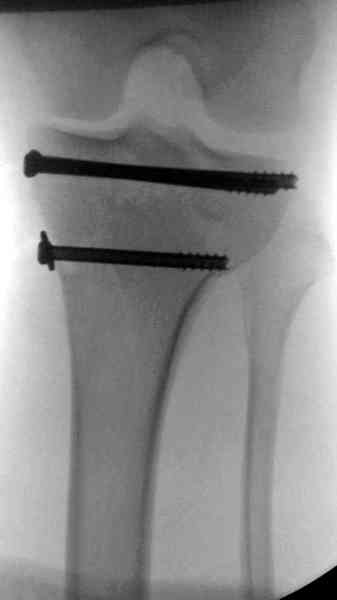

Пострадавшему 21 г., травма скоростная, после I&D с расширением раны, на бедре сделана операция ретроградным интрамедуллярным штифтом, остеосинтез с частичной резекцией надколенника и ушивание собственной связки.

На голень наружный фиксатор, рану на бедре ушили (рана была изнутри кнаружи всего 2 см). По протоколу травматических больных, до операции обследован ангиографически, (у больного дистально не смогли определить пульсацию) сосудистый хирург подтвердил проходимость на всем протяжении магистрального сосуда нижней конечности по снимкам ангиограмм.

В настоящее время больной в реанимации по поводу Черепно Мозговой Травмы и состояние улучшается. Запланировал ушивание раны в пятницу, если позволит состояние мягких тканей и при отсутстви отека возможно удастся просунуть перкутанномедиальную пластину.